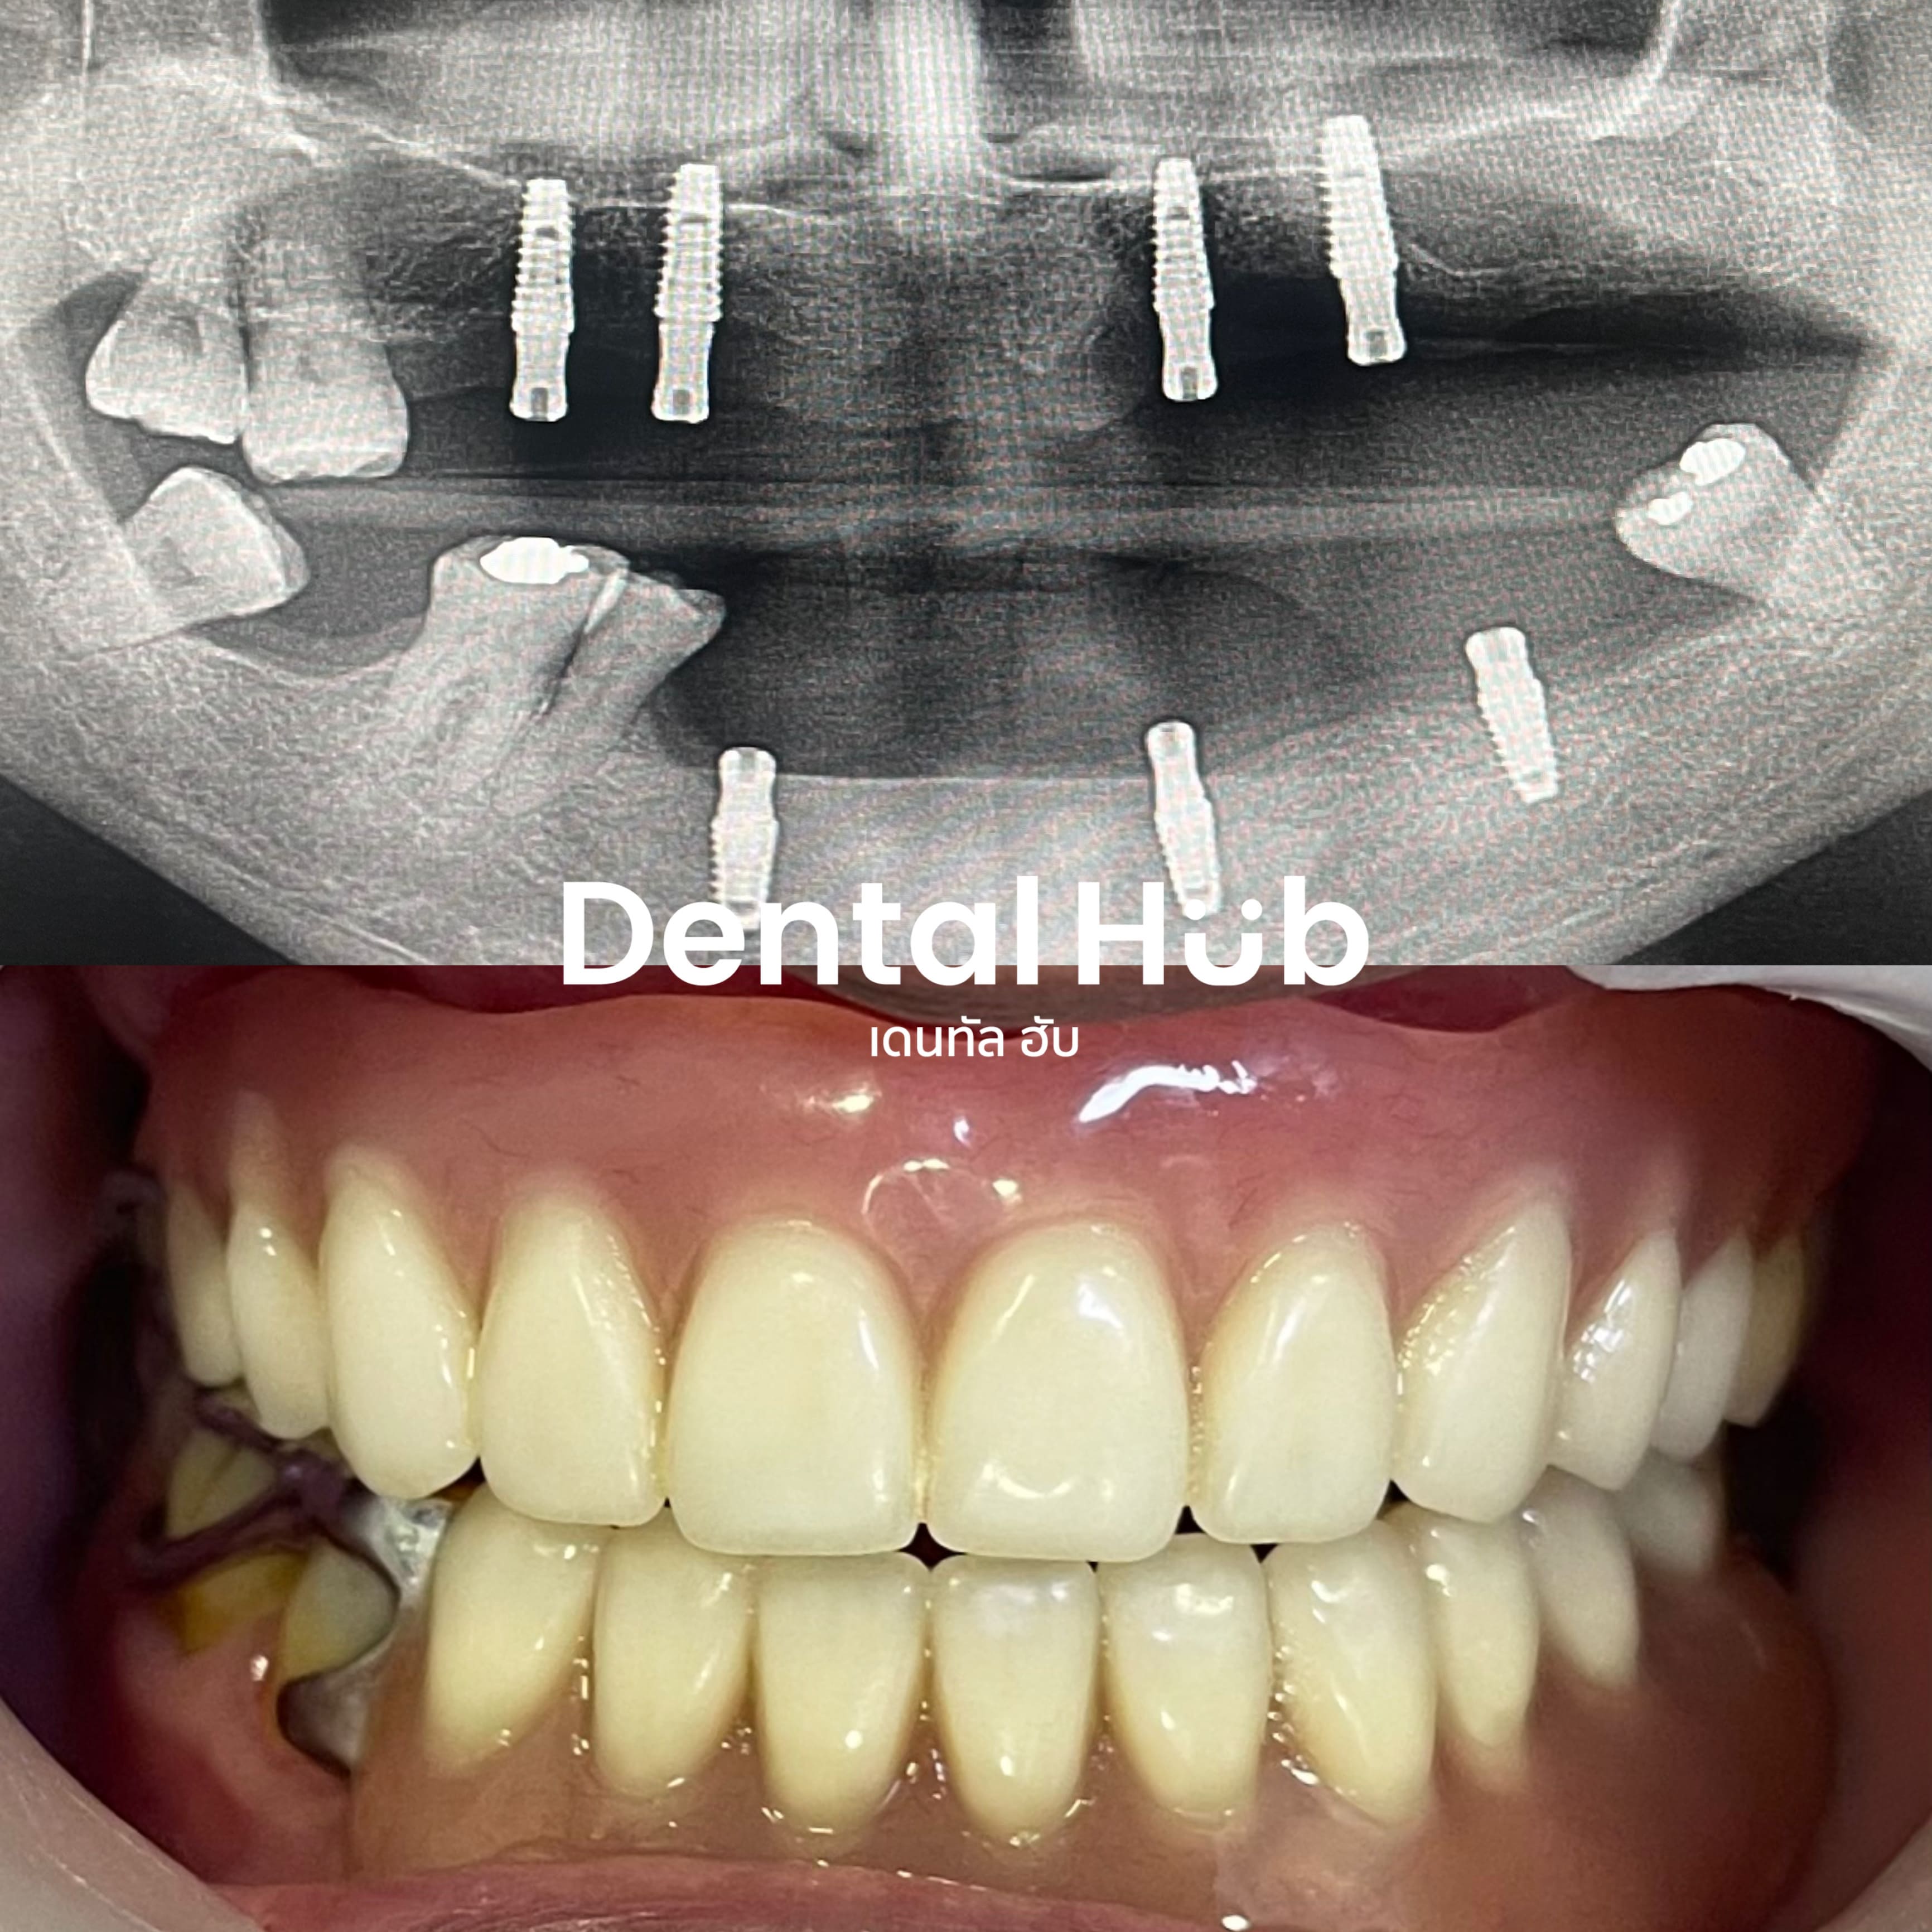

รากฟันเทียม เป็นฟันปลอมแบบติดแน่น โดยฝังแกนไททาเนี่ยมซึ่งเป็นวัสดุที่เข้ากับเนื้อเยื่อร่างกายได้ดี ลงในกระดูกบริเวณช่องว่างที่ไม่มีฟัน และทำตัวครอบฟันต่อสวมบนรากฟันเทียมเพื่อใช้บดเคี้ยวและความสวยงาม

เคสฟันปลอมเสริมรากฟันเทียม

ระบบดิจิทัล การรักษาที่แม่นยำที่สุด

ในเคสที่ซับซ้อน ทางคลินิกมีระบบการฝังร่วมกับการวางแผนสามมิติผ่านคอมพิวเตอร์ ทำให้การรักษา